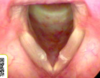

Q

A

Otomicosis